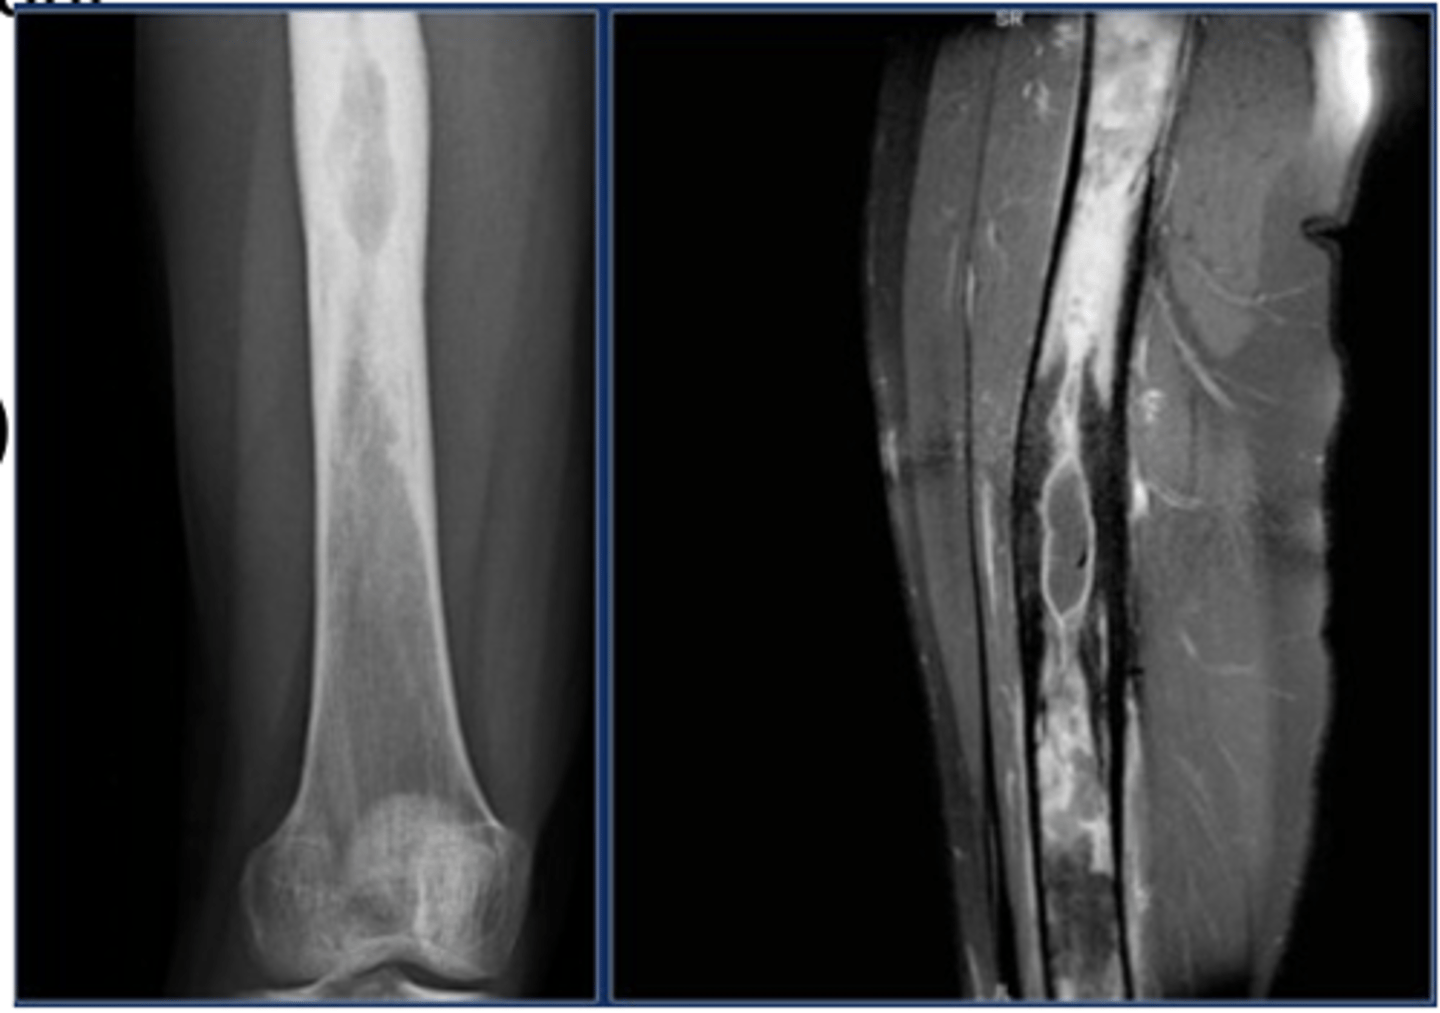

osteomyelitis

Acute or chronic infection of the bone and marrow

Pyogenic - Staphylococcus aureus is most common cause

-- Hematogenous- Originates with infectious organisms that reach the bone through the bloodstream.

-- After open fracture, bacteria from patient’s skin run high risk of establishing colonies inside the bone

Symptoms:

- Bacteremia (chills, fever, malaise)

- Bone lesion (pain, reduced motion)

Treatment:

- Identify causative organism

- Treat organism (e.g., antibiotic)

- Rest & pain management

Possible drainage